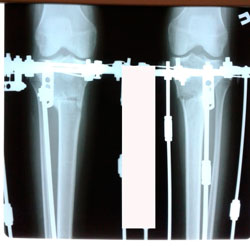

Дата операции - 08.06.2020

Дата снятия аппаратов 24.08.2020

Срок сращения - 75 дней.